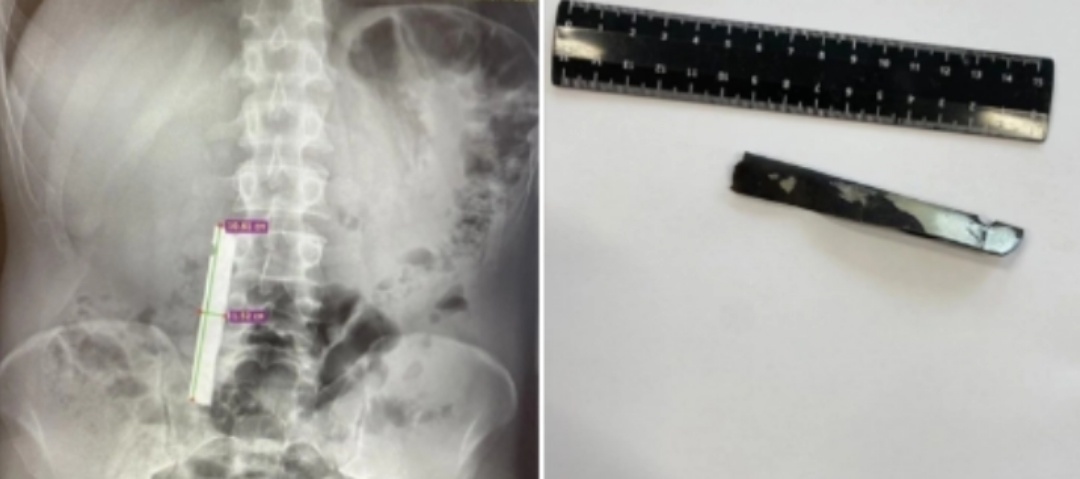

Врачи Советской районной больницы успешно провели сложную операцию по извлечению крупного инородного тела из двенадцатиперстной кишки мужчины.

При обследовании пациента рентген показал наличие металлического предмета в верхних отделах желудочно-кишечного тракта — девять сантиметров в длину, сантиметр в ширину. В экстренном порядке была проведена эзофагогастродуоденоскопия.

Под общим наркозом благодаря слаженной работе команды хирургов и анестезиолога Александра Кобзева инородное тело было успешно удалено. Повреждений органов не выявлено.

Заведующий хирургическим отделением Иван Папалуца отметил, что операция прошла успешно благодаря круглосуточной эндоскопической службе и командной работе медперсонала — Марине Гатиятовой и Галине Поповой.